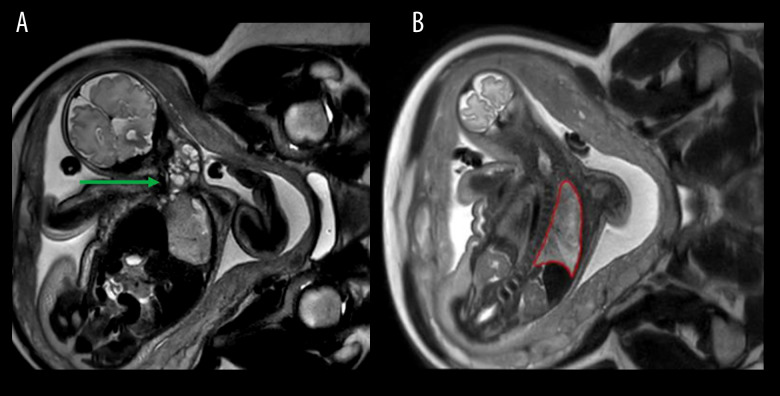

背景:在潜在的产后气道阻塞的情况下,宫内气管治疗(EXIT)是一项复杂的围产期手术。它需要一个经验丰富的多学科团队和基于胎儿成像的细致的手术计划。本报告描述了使用出口到气道的大宫颈畸胎瘤延伸到纵隔。病例报告:在妊娠35周时,一名29岁的女性因羊水过多来到我们的胎儿护理中心。胎儿随后被诊断为一个大的宫颈肿块延伸到纵隔。妊娠36周时进行出口至气道手术。在获得产后成像时,新生儿仍插管。在出生第3天,通过宫颈和纵隔联合入路切除畸胎瘤。病理证实为成熟畸胎瘤。新生儿的住院过程因吸入和喂养而变得复杂,需要胃造口管,她在出生第40天出院。结论:虽然宫颈畸胎瘤是EXIT手术的一个明确的适应症,但该病例因其妊娠晚期晚期的诊断和罕见的肿块延伸到纵隔,需要双重手术入路。它强调了在反复发生的晚期羊水过多的情况下维持广泛的鉴别诊断的重要性,并证明了多学科计划在预期气道损害时优化结果的关键作用。本病例提供了越来越多的证据,支持在复杂的颈纵隔肿块中扩大出口到气道的应用。

BACKGROUND Ex-utero intrapartum treatment (EXIT)-to-airway is a complex perinatal procedure performed in the case of potential postnatal airway obstruction. It requires an experienced multidisciplinary team and meticulous surgical planning based on fetal imaging. This report describes the use of EXIT-to-airway for a large cervical teratoma with extension into the mediastinum. CASE REPORT At 35 weeks' gestation, a 29-year-old woman presented to our fetal care center with significant polyhydramnios. The fetus was subsequently diagnosed with a large cervical mass extending into the mediastinum. An EXIT-to-airway procedure was performed at 36 weeks' gestation. The neonate remained intubated while postnatal imaging was obtained. At day of life 3, resection of the teratoma was performed via a combined cervical and mediastinal approach. Pathology confirmed a mature teratoma. The neonate's hospital course was complicated by aspiration with feeding, requiring a gastrostomy tube, and she was discharged on day of life 40. CONCLUSIONS While cervical teratoma is a well-established indication for the EXIT procedure, this case is notable for its late third-trimester diagnosis and the rare extension of the mass into the mediastinum, which necessitated a dual surgical approach. It highlights the importance of maintaining a broad differential diagnosis in the setting of recurrent third-trimester polyhydramnios and demonstrates the critical role of multidisciplinary planning in optimizing outcomes when airway compromise is anticipated. This case contributes to the growing body of evidence supporting the expanded utility of EXIT-to-airway for complex cervicomediastinal masses.